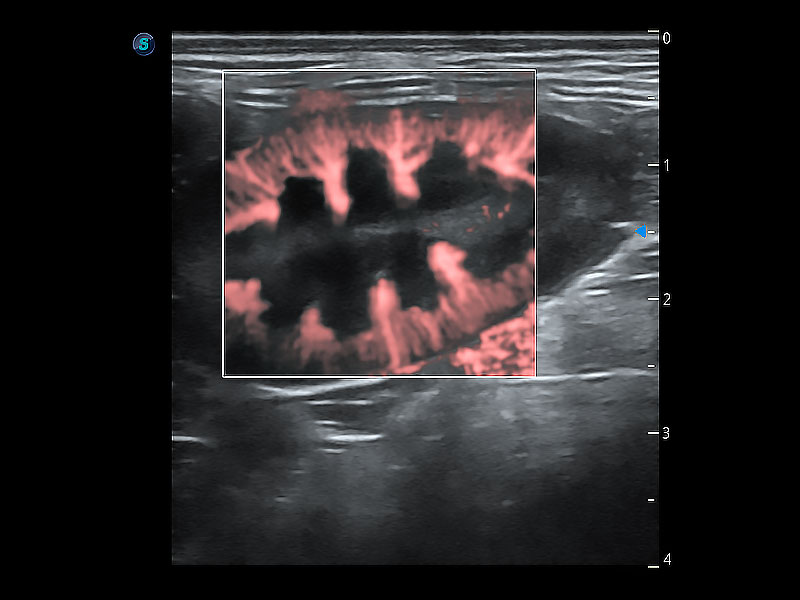

极大提升超低速微细血流的检出能力,同时更精准地滤除软组织和超声信号,为兽用医生提供以往无法通过常规血流获得的疾病诊断信息。

非线性融合造影成像充分利用谐波和基波信号,为难以观察的血流进行增强显像。可用于线阵、凸阵、微凸阵、相控阵探头。